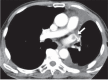

Figure 2. CT scan of the chest with IV contrast

A thrombus (white arrow) in the left superior pulmonary vein stump after left upper lobectomy [6].